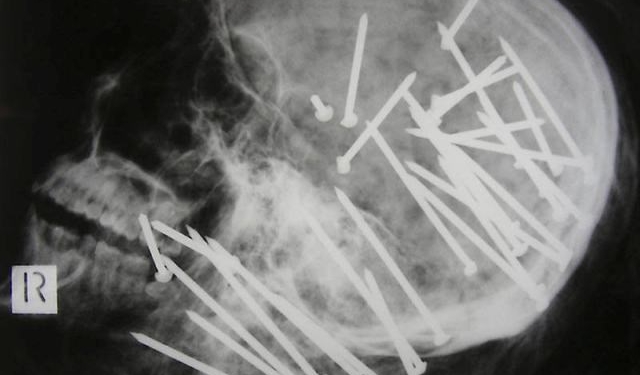

9. Pregos na cabeça

Esse chinês chegou ao hospital com uma queixa de dor de cabeça e uma explicação: ele havia se acidentado com um pinador pneumático. Assustador, não?